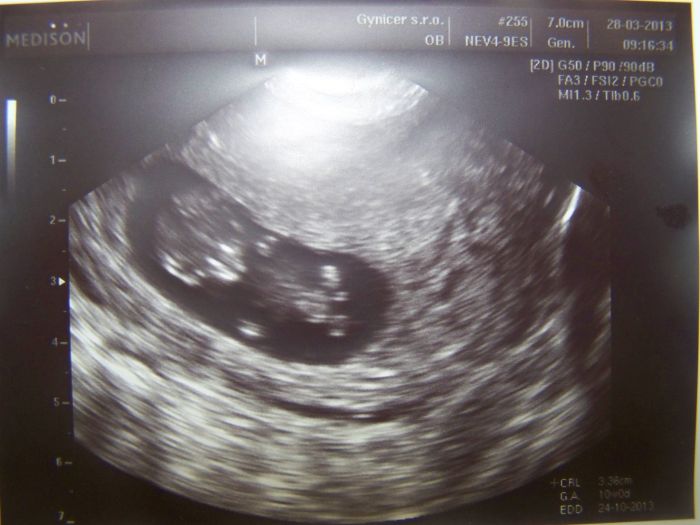

tak se hlásím po delší době. Zkoukla jsem fotečky UTZ, bříšek i kočárků.

Jsem právě 16tt, bříšenko pomaličku roste, nevolnosti pomalu vymizely, zato mě chytají ty pravé těhu chutě :-) Na váhu raději nejdu, abych se nevyděsila, haha. Ale naposled jsem měla 76kg, na poradnu a UTZ jdu 9.5. tak jsem zvědavá, zda mi u řekne, kdopak se nám to v bříšku schovává. Jinak už jsem taky neodolala a máme náš vysněný kočárek doma :-) s nákupem věciček čekám, máme toho dost po Matyáškovi, jsou tam i neutrální věcičky, no a kdyby to byla slečna, tak mám dodavatelku kamarádku, jejíž holčička bude mít v době narození našeho miminka právě roček.

Dám vám sem fotečky UTZ a kočárku a ve čtvrtek napíšu novinky z poradny.